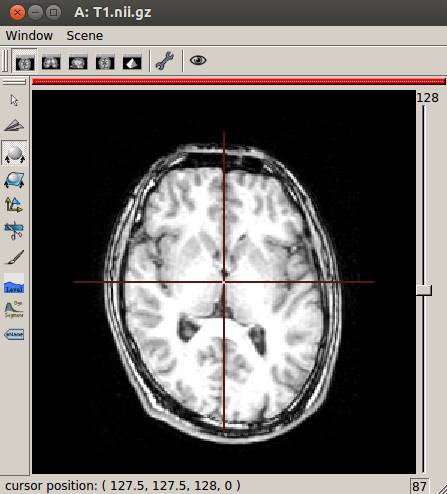

mri_convert

T1.mgz T1.nii.gz

Anatomistで開いたところです。